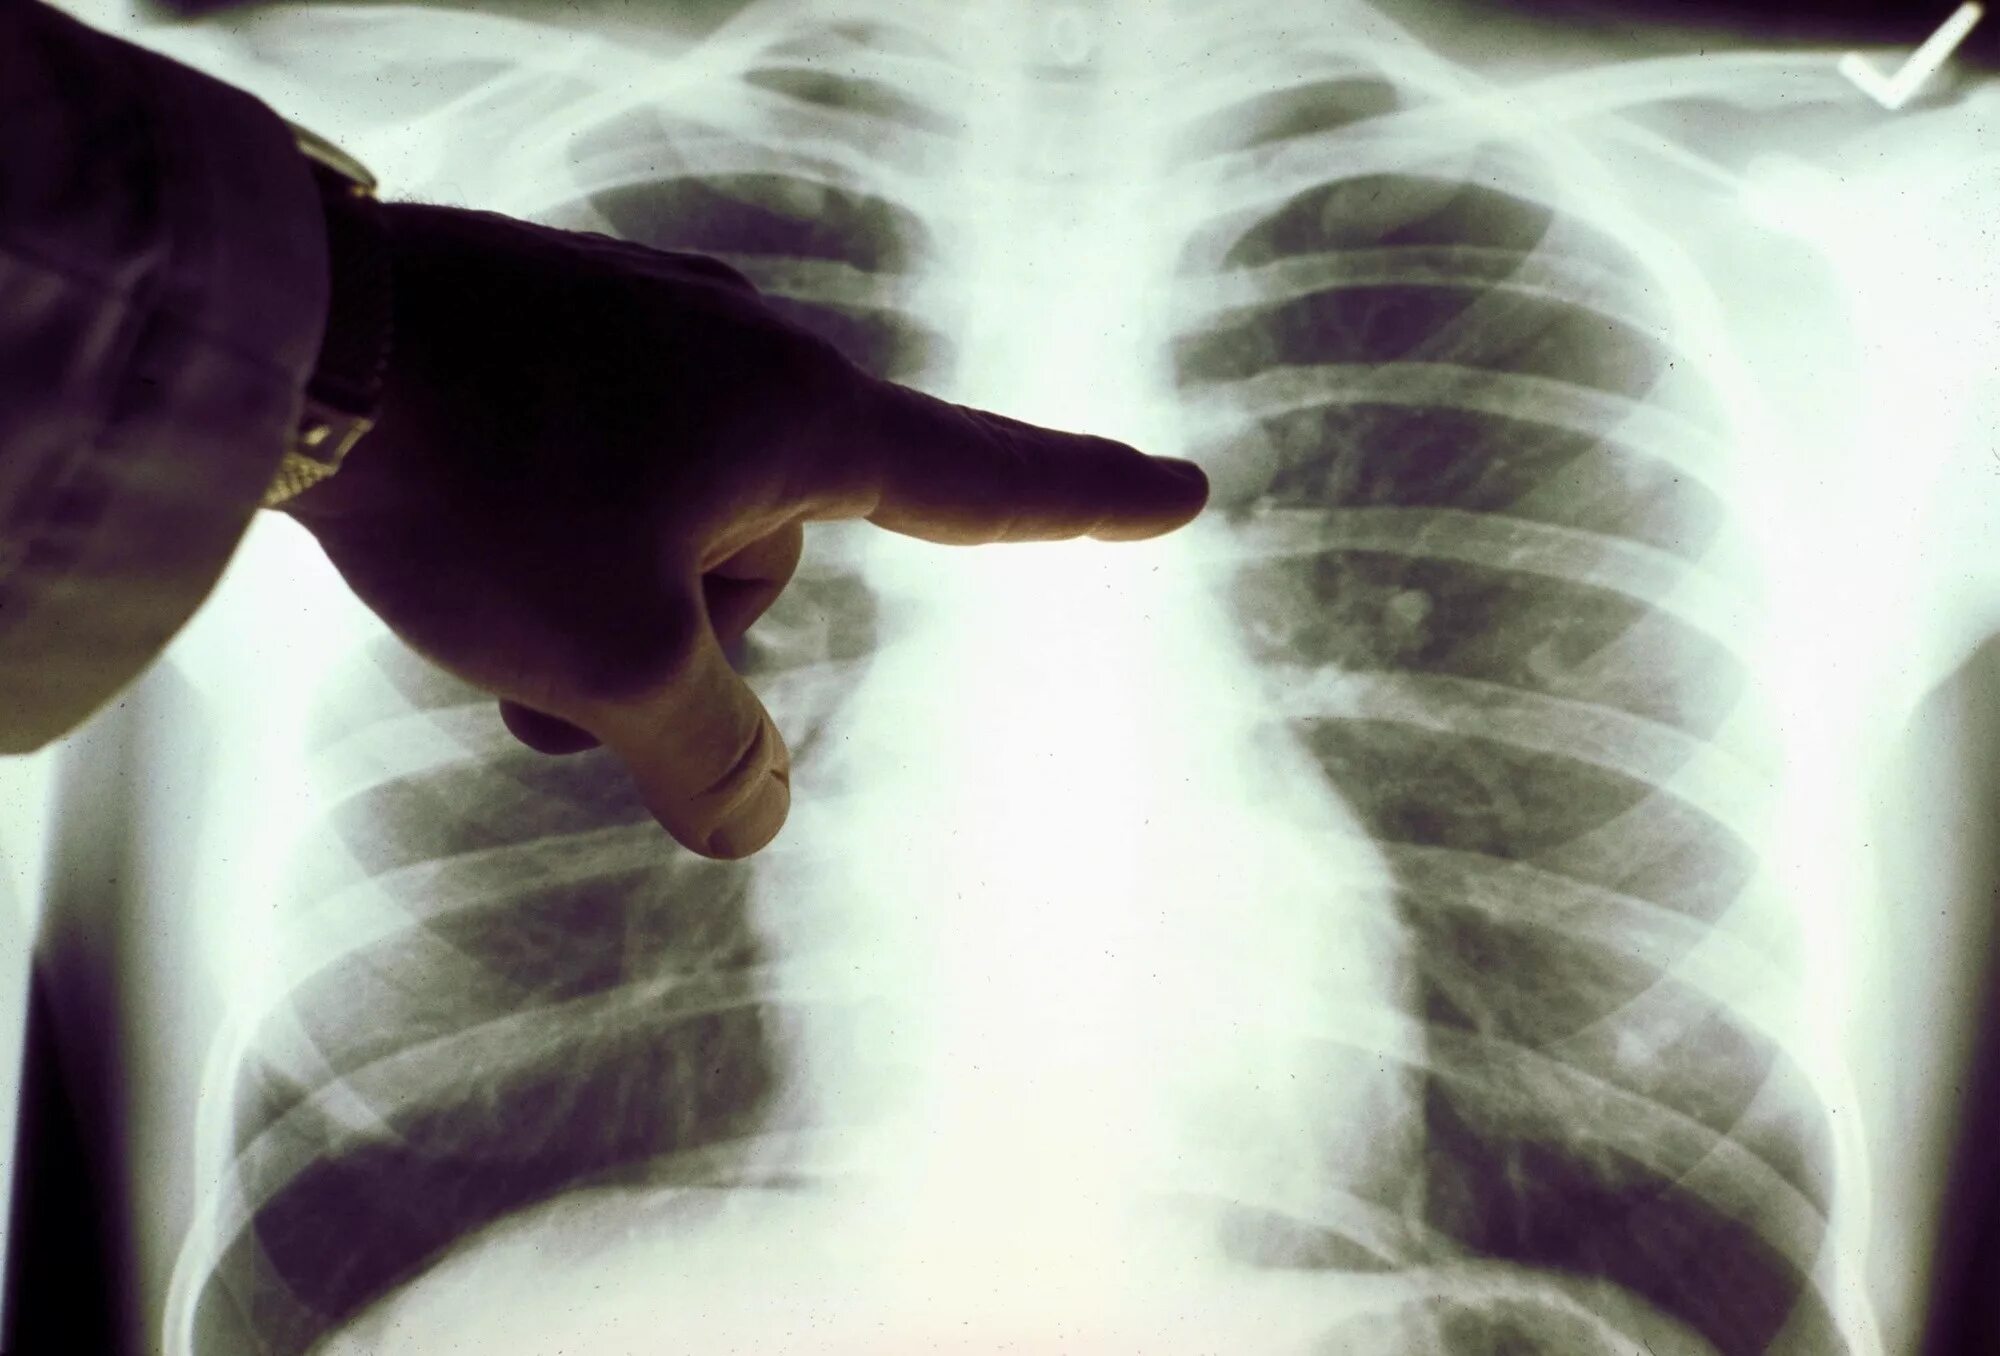

Почему в легких